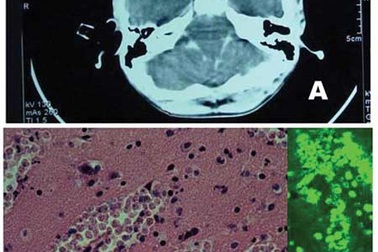

Bộ Y tế xác nhận bệnh nhi 6 tuổi tử vong vì “amíp ăn não”Sáng 19/9, Bộ Y tế xác nhận, kết quả xét nghiệm mẫu bệnh phẩm của bệnh nhi 6 tuổi tử vong tại TP Hồ Chí Minh do bị áp xe não là vì nhiễm amíp Naegleria Fowler (hay còn được gọi là amip ăn não người).